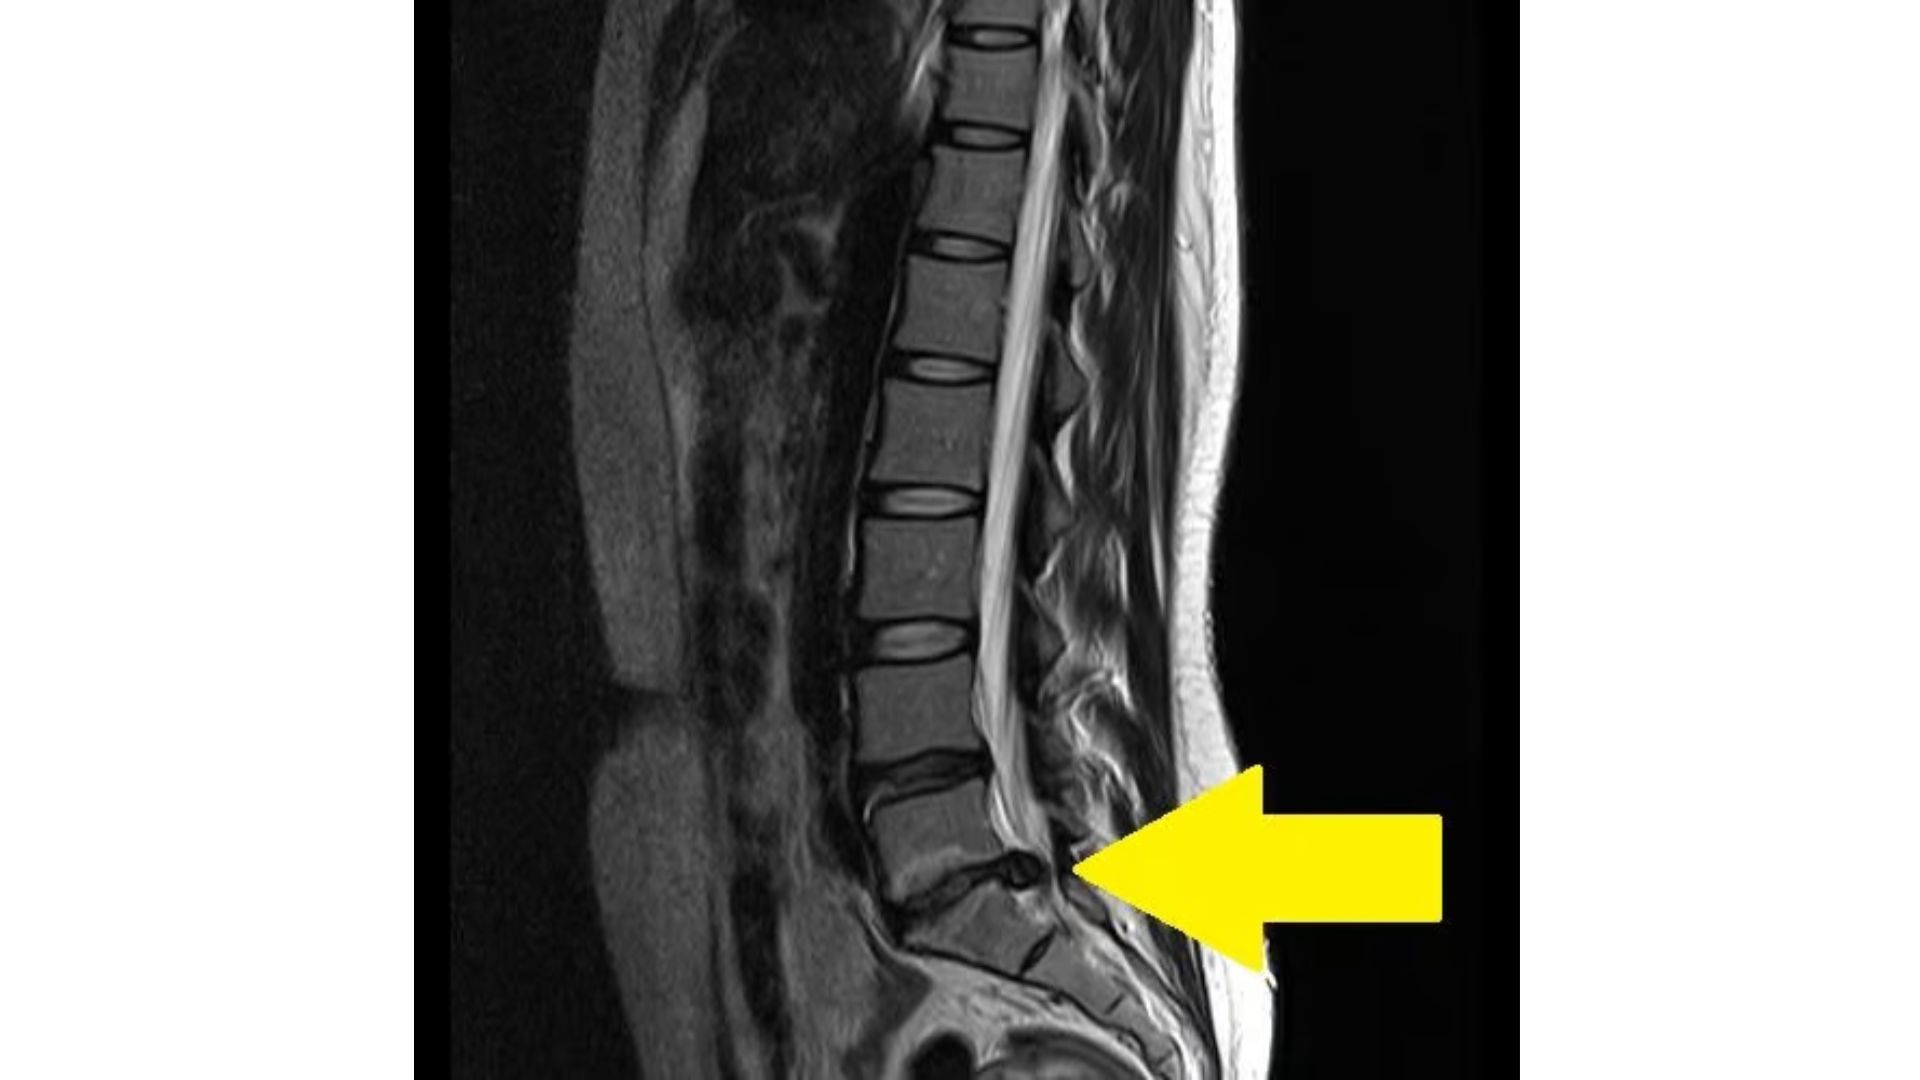

椎間板ヘルニアとは、背骨の間にある「クッション」の役割をする椎間板が変形し、神経を「ギューッ」と圧迫する状態です。この状態が続くと、腰や足に強い痛みやしびれが現れ、日常生活に大きな影響を及ぼすことがあります。

急に重い荷物を持ち上げたり、「ハクション!」とくしゃみをした時に腰に「ズキン」とした痛みを感じたことはありませんか?これが急性型の椎間板ヘルニアの特徴です。また、慢性型では痛みがじわじわと続き、神経の圧迫により足にしびれや筋力低下が起こることもあります。

保存療法で改善が見られない場合には、手術療法が考慮されることがあります。手術では、変形した椎間板の一部を除去し、神経の圧迫を解消しますが、手術にはリスクも伴います。だからこそ、手術後のリハビリが重要で、体を少しずつ元の状態に戻していくサポートが欠かせません。